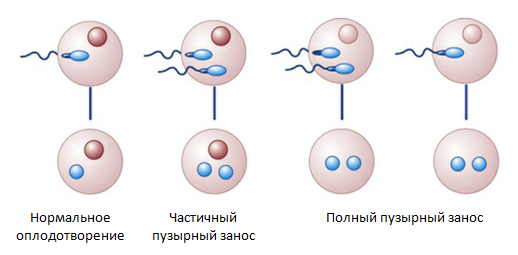

Медицина и диагностика: Инвазивный пузырный занос на УЗИ

Раздел: Альбом идей